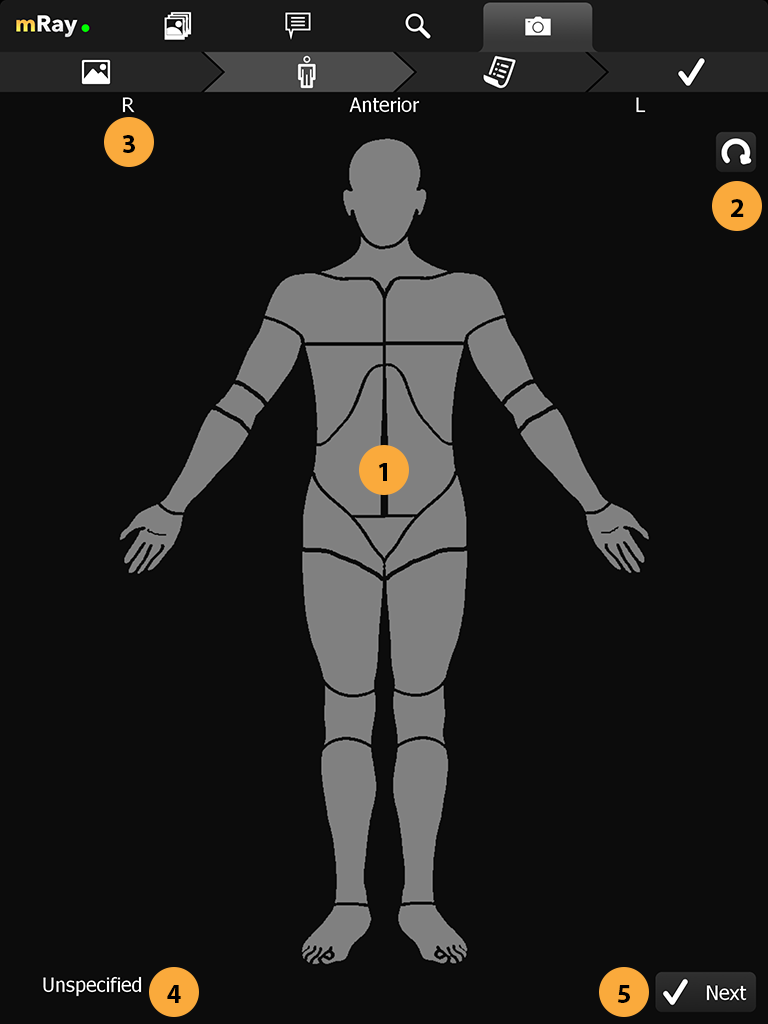

15. Photo documentation

|

The photo documentation feature is expressly not permitted for diagnosis or treatment decisions. This feature isn’t enabled by default. It is only available for evaluation purposes. If you’re interested in taking part of the evaluation, please contact your mbits support staff. |

When the feature is enabled for the current user you’ll see an extra tab for the photo documentation and a button in your inbox to open the camera. By pressing on the camera button (Point 2) you’ll open the camera and be able to capture all the photos you require. A photo documentation workflow will be like the following

-

Take pictures

-

Select photos that should be assigned to a patient or order

-

Select the body part which reflects the content of the photos

-

Select a patient or order

-

Add more information to the photos (key wording)

-

Confirmation

-

Wait a moment for the photos to appear in the inbox

-

Go to the Photo documentation tab

-

Open the Photo documentation camera

15.1. Camera

When you’ve captured all the photos you need press the photo stack (Point 3) to continue to the review process.

-

Shutter button to capture a image.

-

Select desired camera lens (only on devices with more than one camera).

-

Image stack of taken images. Click to return to gallery.

-

Enable, disable or set automatic flash operation.

-

Enable or disable automatic white balance adjustment.

-

Enable or disable automatic exposure adjustment.